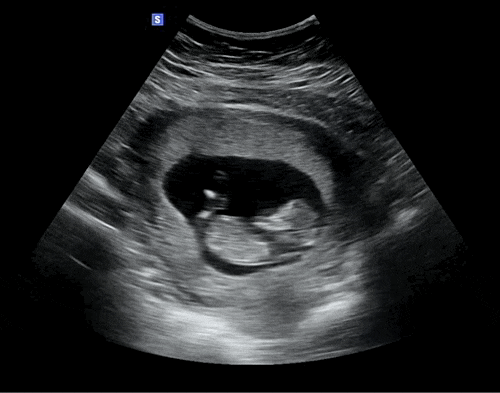

[임신 23~26주] 정신없이 쏘다니는 임신중기 / 입체초음파, 임당, 임당재검

두달이 지나서 쓰는 가물가물한 임신중기 일상 > < 8월말~9월은 그간 미뤄놨던 여행 계획이 가득가득...

[임신 20~22주] 시간이 너무 빠른 임신중기(정밀초음파 후기, 임신중 파마)

시간이 점점 빨라지는 것 같다 임신 4주에 처음 알게 되어 벌써 임신 20주라니 ? 아가가 태어나기 전 시...